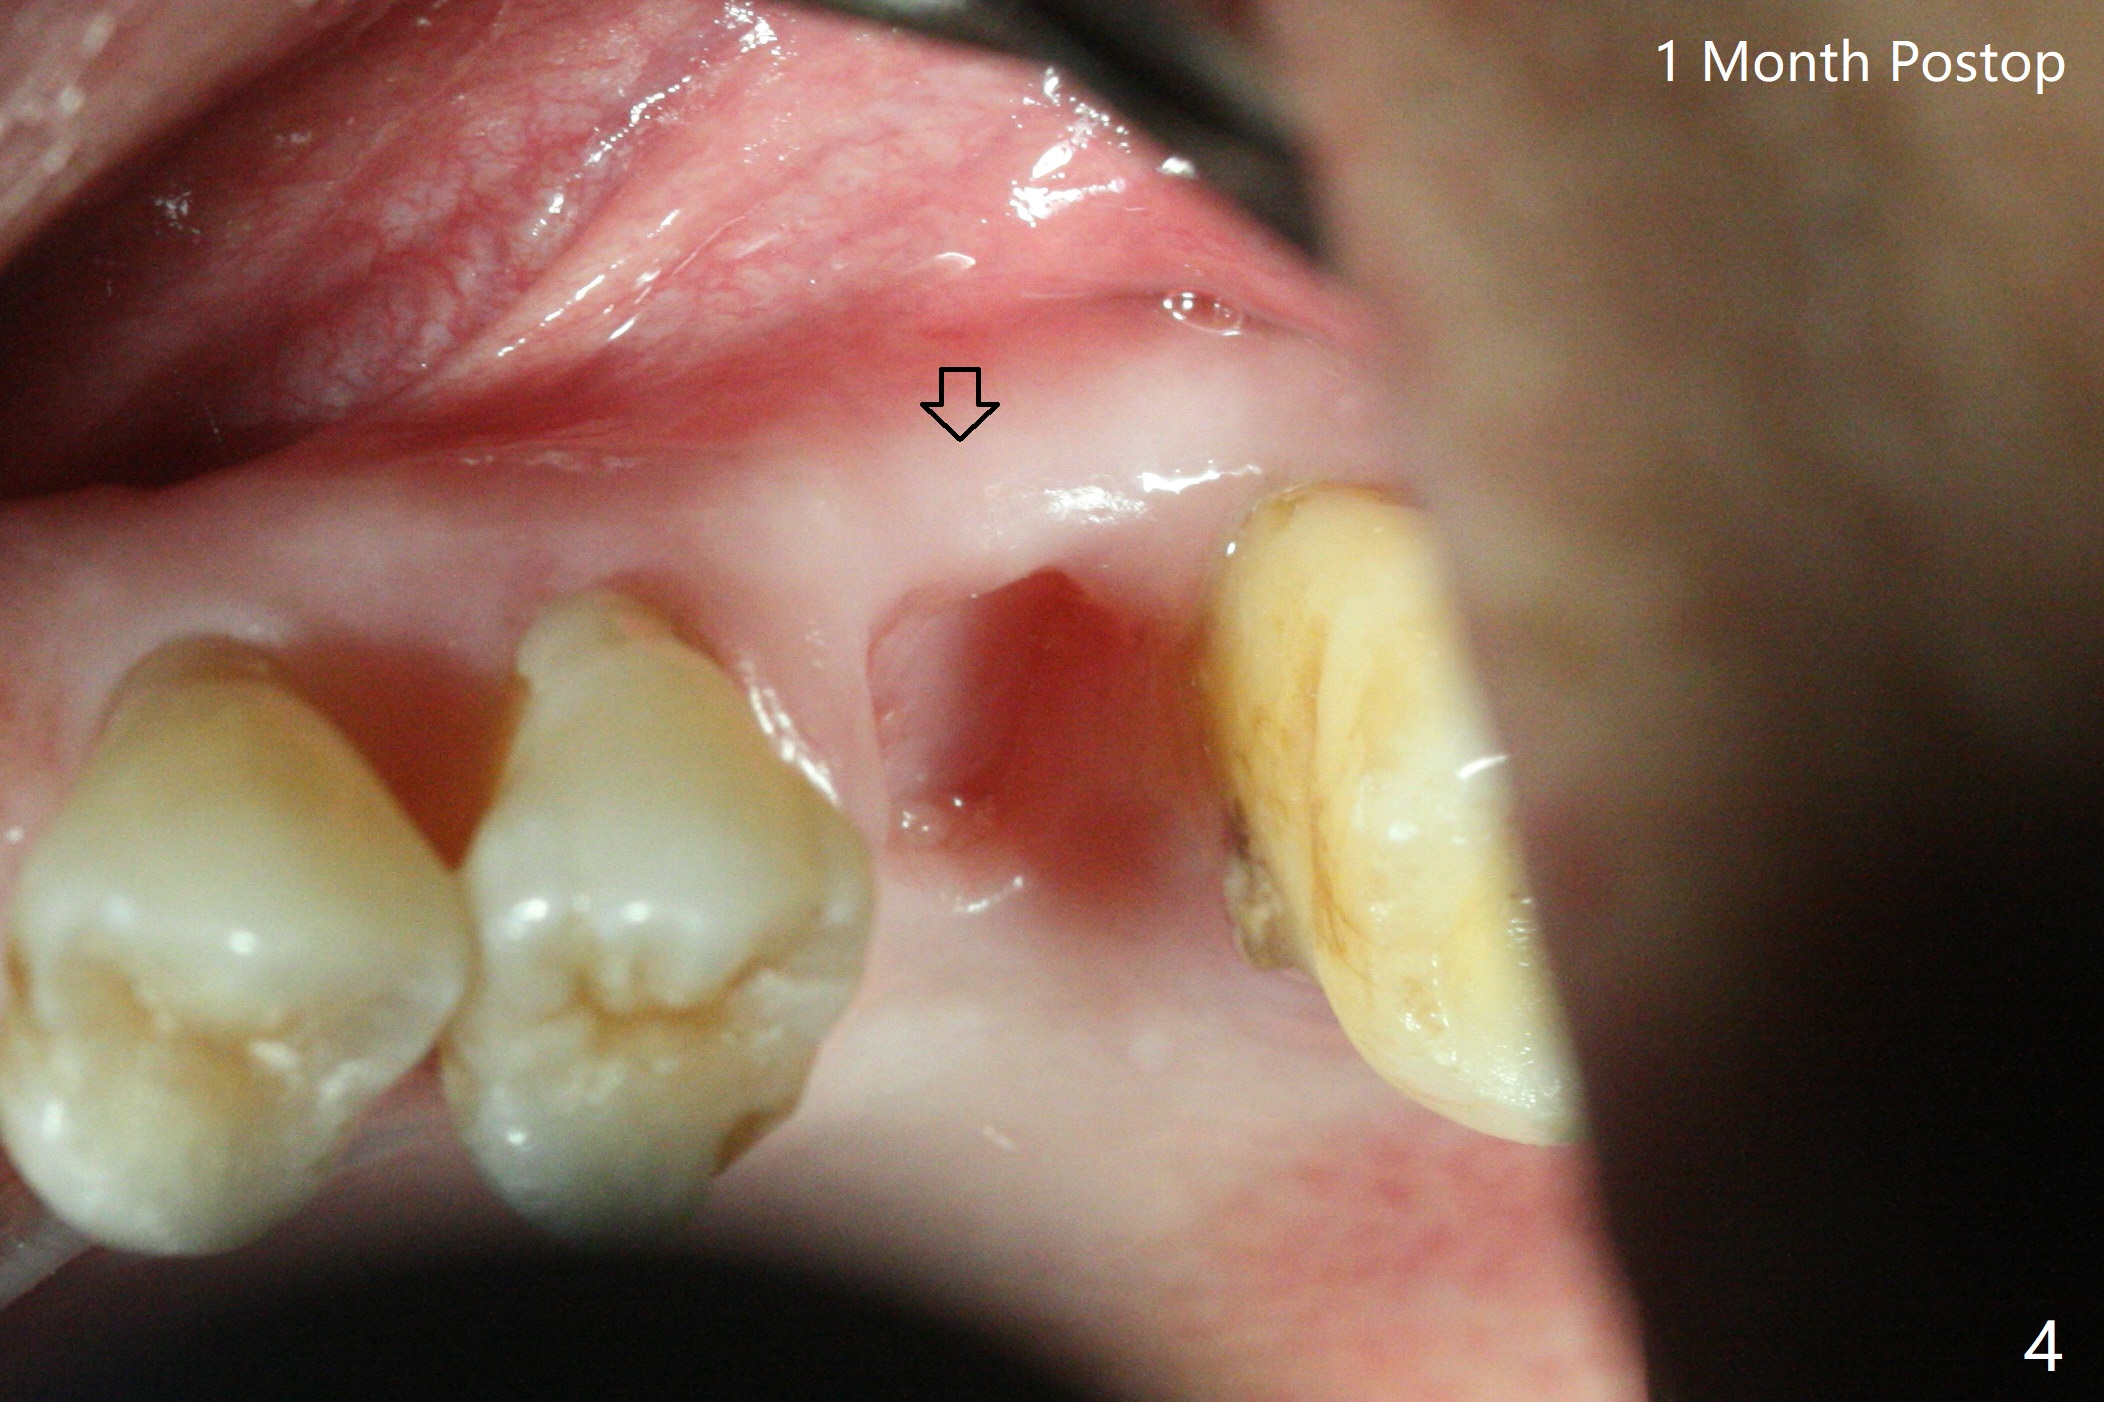

64岁男左上6疼痛(图一),可能继发于牙周病-牙髓炎综合征以及咬合创伤(右上2缺失),深洗,咬合调整后无效,要求拔除,经过解释,同意植骨,颊侧,腭侧骨板均有破坏,中隔正常,放置粘性骨粉后(图二),覆盖PRF膜(图三:>)和GEM Cap (C,9-12个月可吸收膜,Curves when hydrated to facilitate placement),牙周胶水固定(节省时间)。最后牙周敷料(进入左上3残根间隙)。术后两个星期牙周敷料脱落,一个月颊侧骨板开始塌陷(图四:箭头)。